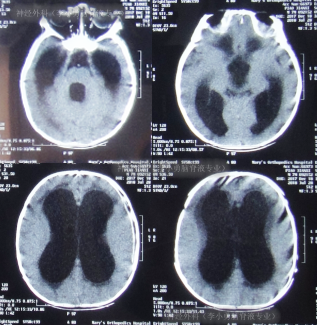

图-3:2018年7月28日头颅CT

入院当天进行了脑室外引流术,术后第1天即2018年7月29日,查头颅CT示脑室引流术状态(图-4)。

图-4:2018年7月29日头颅CT